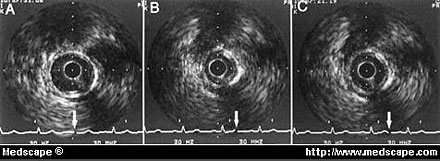

Representative pattern of intravascular ultrasound imaging at site with CMB.

A, At end diastole, cross-sectional area was 6.85 mm2.

B, In systole, area was significantly narrowed to 2.32 mm2.

C, Narrowing continued until early diastole. No intimal thickening was found at the CMB site.